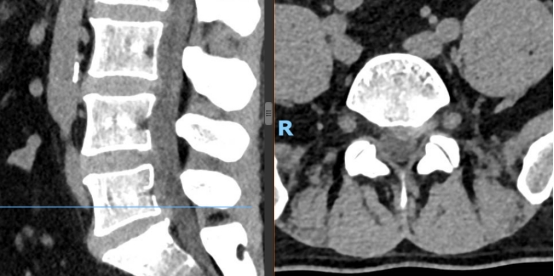

如果说UBE技术是脊柱治疗的“精准镜手”,那么3D打印技术就是定制化治疗的“私人裁缝”。针对每一位脊柱疾病患者的个体差异,医生通过高精度CT扫描,获取患者脊柱的三维立体数据,利用3D打印技术1:1还原脊柱的解剖结构——从椎体形态、椎间盘位置,到神经走行、病变范围,都能精准复刻,形成专属的脊柱模型。基于此模型,医生术前可以进行精准规划:模拟手术路径、预判操作风险、选择适配的内固定器械,甚至打印定制化的椎间融合器、内固定支架,确保手术操作“有的放矢”,贴合患者的个体解剖特征,避免传统手术中“凭经验操作”的不确定性,让脊柱治疗从“标准化”走向“个性化”,极大提升了手术的精准度与安全性。

1.术前规划更精准:通过3D打印脊柱模型,医生可直观掌握患者的病变细节,提前设计最佳手术路径,避开神经、血管等重要组织,降低手术风险;

2.术中操作更精准:在UBE高清内镜视野下,结合3D打印模型的术前预判,医生可精准切除病变组织、植入定制化内固定物,减少对正常脊柱结构的损伤;